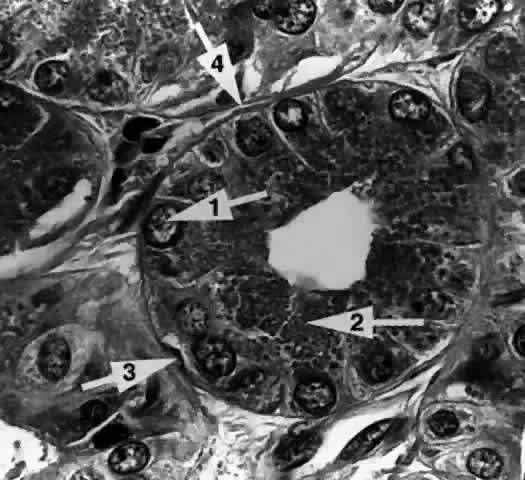

The Acinar Unit (Fig. 13)

Each lobule consists of a complicated grape-like (Fig. 14) arrangement of acini. Each acinar unit (Fig. 15) consists of a central lumen, a continuous inner layer of columnar secretory epithelial cells, and a surrounding interrupted outer layer of irregularly shaped myoepithelial (basket) cells.9

Fig. 15. The acinar unit. The columnar secretory cell has a basally located nucleus (arrow 1). Zymogenic secretory granules (arrow 2) are seen in the midportion and apical cytoplasm. A myoepithelial cell (arrow 3) is interspersed between the secretory cell and the basement membrane (arrow 4). (H & E, original magnification × 250; Courtesy of Ralph Eagle, MD, Philadelphia, PA)

The acinar secretory cell typically has a basally located nucleus with one or two nucleoli, as seen with electron microscopy. The predominant structures in its cytoplasm are the numerous zymogenic secretory granules located mainly in the apical or midportions of the cell9 (see Fig. 15).

Myoepithelial cells (see Fig. 15) appear as flattened, stellate, or spindle-shaped cells interspersed in the basal part of the acinar wall, between the secretory cells and the basement membrane. They are characterized by the presence of cytoplasmic myofilaments. The myofilaments consist of actin-type filaments in a parallel fashion, in some areas resembling fusiform smooth muscle.9,11

A thick, often multilayered basement membrane (see Fig. 15) surrounds the outer surface of the acinus, separating it from the intralobular connective tissue. Collagen fibrils, capillaries, unmyelinated nerve fibers, fibroblasts, plasma cells, and lymphocytes can be found within this connective tissue. The plasma cells have been shown to produce IgA, an immunoglobulin typically elaborated at mucosal surfaces. Acetylcholinesterase activity has been found around the acini, particularly adjacent to the myoepithelial cells, suggesting that they are the primary neural target for parasympathetic activity.16,17